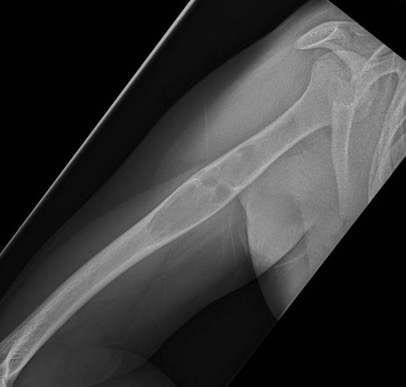

X-ray

Well-defined lucency

- thin sclerotic rim

- usually central

- thinned cortex with slight expansion

- thin internal septa

- can be multi-loculated

Fallen-Leaf (AKA fallen-fragment)

- with pathological fracture

- indicates that the lesion has no matrix and is fluid filled

Fallen leaf sign